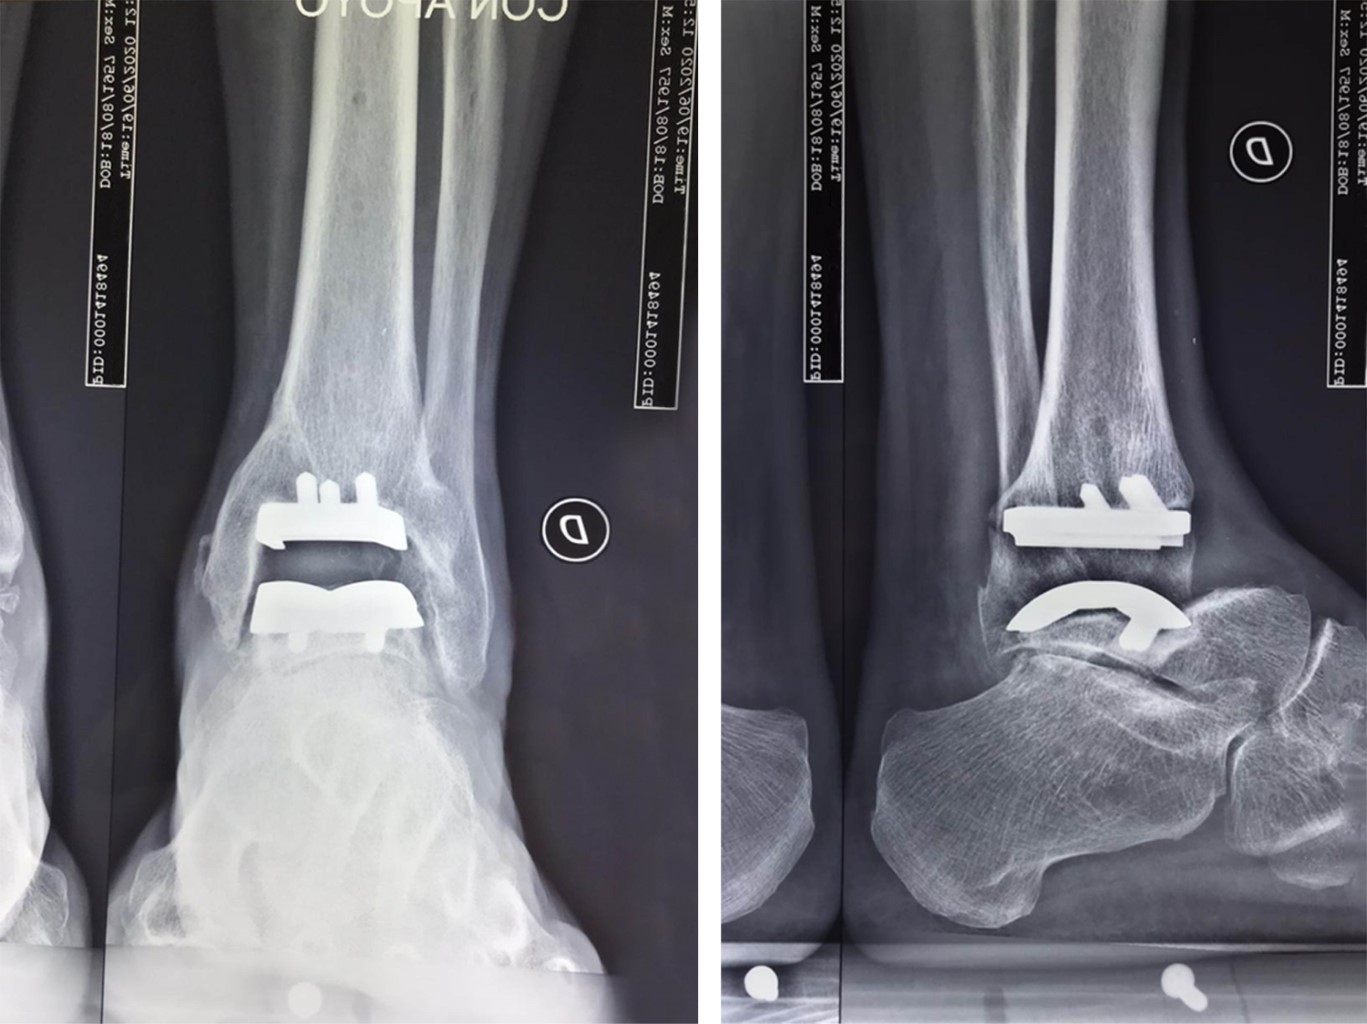

Bajo anestesia regional, en decúbito dorsal e isquemia neumática, se practicó abordaje dorsal al tobillo, se incidió retináculo extensor con medialización del tendón tibial anterior y lateralización del extensor largo de los dedos junto con el paquete neurovascular del tibial anterior; se identificó el extremo distal de la tibia y los maléolos; se extendió distalmente el abordaje, identificando el cuello del astrágalo y la articulación talo-navicular; con visión fluoroscópica, se identificó la altura de lo que correspondería a la articulación talo-navicular y a las goteras medial y lateral del tobillo. A continuación, se realizó el procedimiento de acuerdo a la técnica quirúrgica habitual. La posición adecuada del implante protésico de prueba se verificó con fluoroscopia; posteriormente, se colocaron los implantes definitivos. Para la estabilización de la articulación sub-talar se utilizó un sistema de fijación flexible con botones siguiendo la dirección del ligamento cervical (Figura 3).

Figura 3